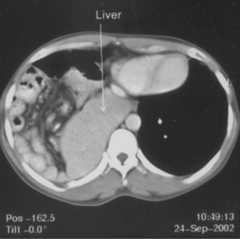

A thirty five year old male presented with breathlessness on routine exertion and symptoms of dyspepsia of a year duration. General physical examination was unremarkable, auscultation of the chest revealed presence of bowel sounds in the right side of the chest. Chest radiograph revealed a raised right hemidiaphragm, with its outlines not well discernible, mediastinal shift to the left and presence of air filled bowel loops in the right thoracic cavity (Fig 1). A provisional diagnosis of right sided diaphragmatic hernia was made and an upper gastrointestinal barium study was done which revealed presence of stomach, small intestine and parts of colon in the right thoracic cavity (Fig 2). A contrast enhanced CT scan of the thorax and abdomen was performed which confirmed presence of stomach, small intestine, large intestine and the right lobe of liver in the postero-lateral aspect of the thoracic cavity, discontinuity of the soft tissue line of the diaphragm with continuity of sub-diaphragmatic and supra-diaphragmatic densities through the defect suggestive of Bochdalek hernia (Fig 3). The right lobe of the liver was also hypoplastic. The patient was taken up for surgery and per operative findings revealed herniation of the stomach, coils of jejunum, ileum and colon through a smooth circular defect of 6cmx4cm size in the posterolateral aspect of the right hemidiphragm. The right lobe of the liver was hypoplastic and had herniated into the thoracic cavity. No hernial sac could be identified. The diaphragmatic defect was closed with polypropylene mesh and sutured in two layers with interrupted non-absorbable suture and the thoracic cavity was drained by a single chest tube. The patient had an uneventful postoperative recovery. A repeat upper GI barium study after 10 days of surgery revealed no evidence of any herniated bowel loop in the thoracic cavity (Fig 4).

Fig. 3.

Contrast enhanced CT of the abdomen showing presence of stomach, small intestine, large intestine and the right lobe of liver in the postero-lateral aspect of the thoracic cavity